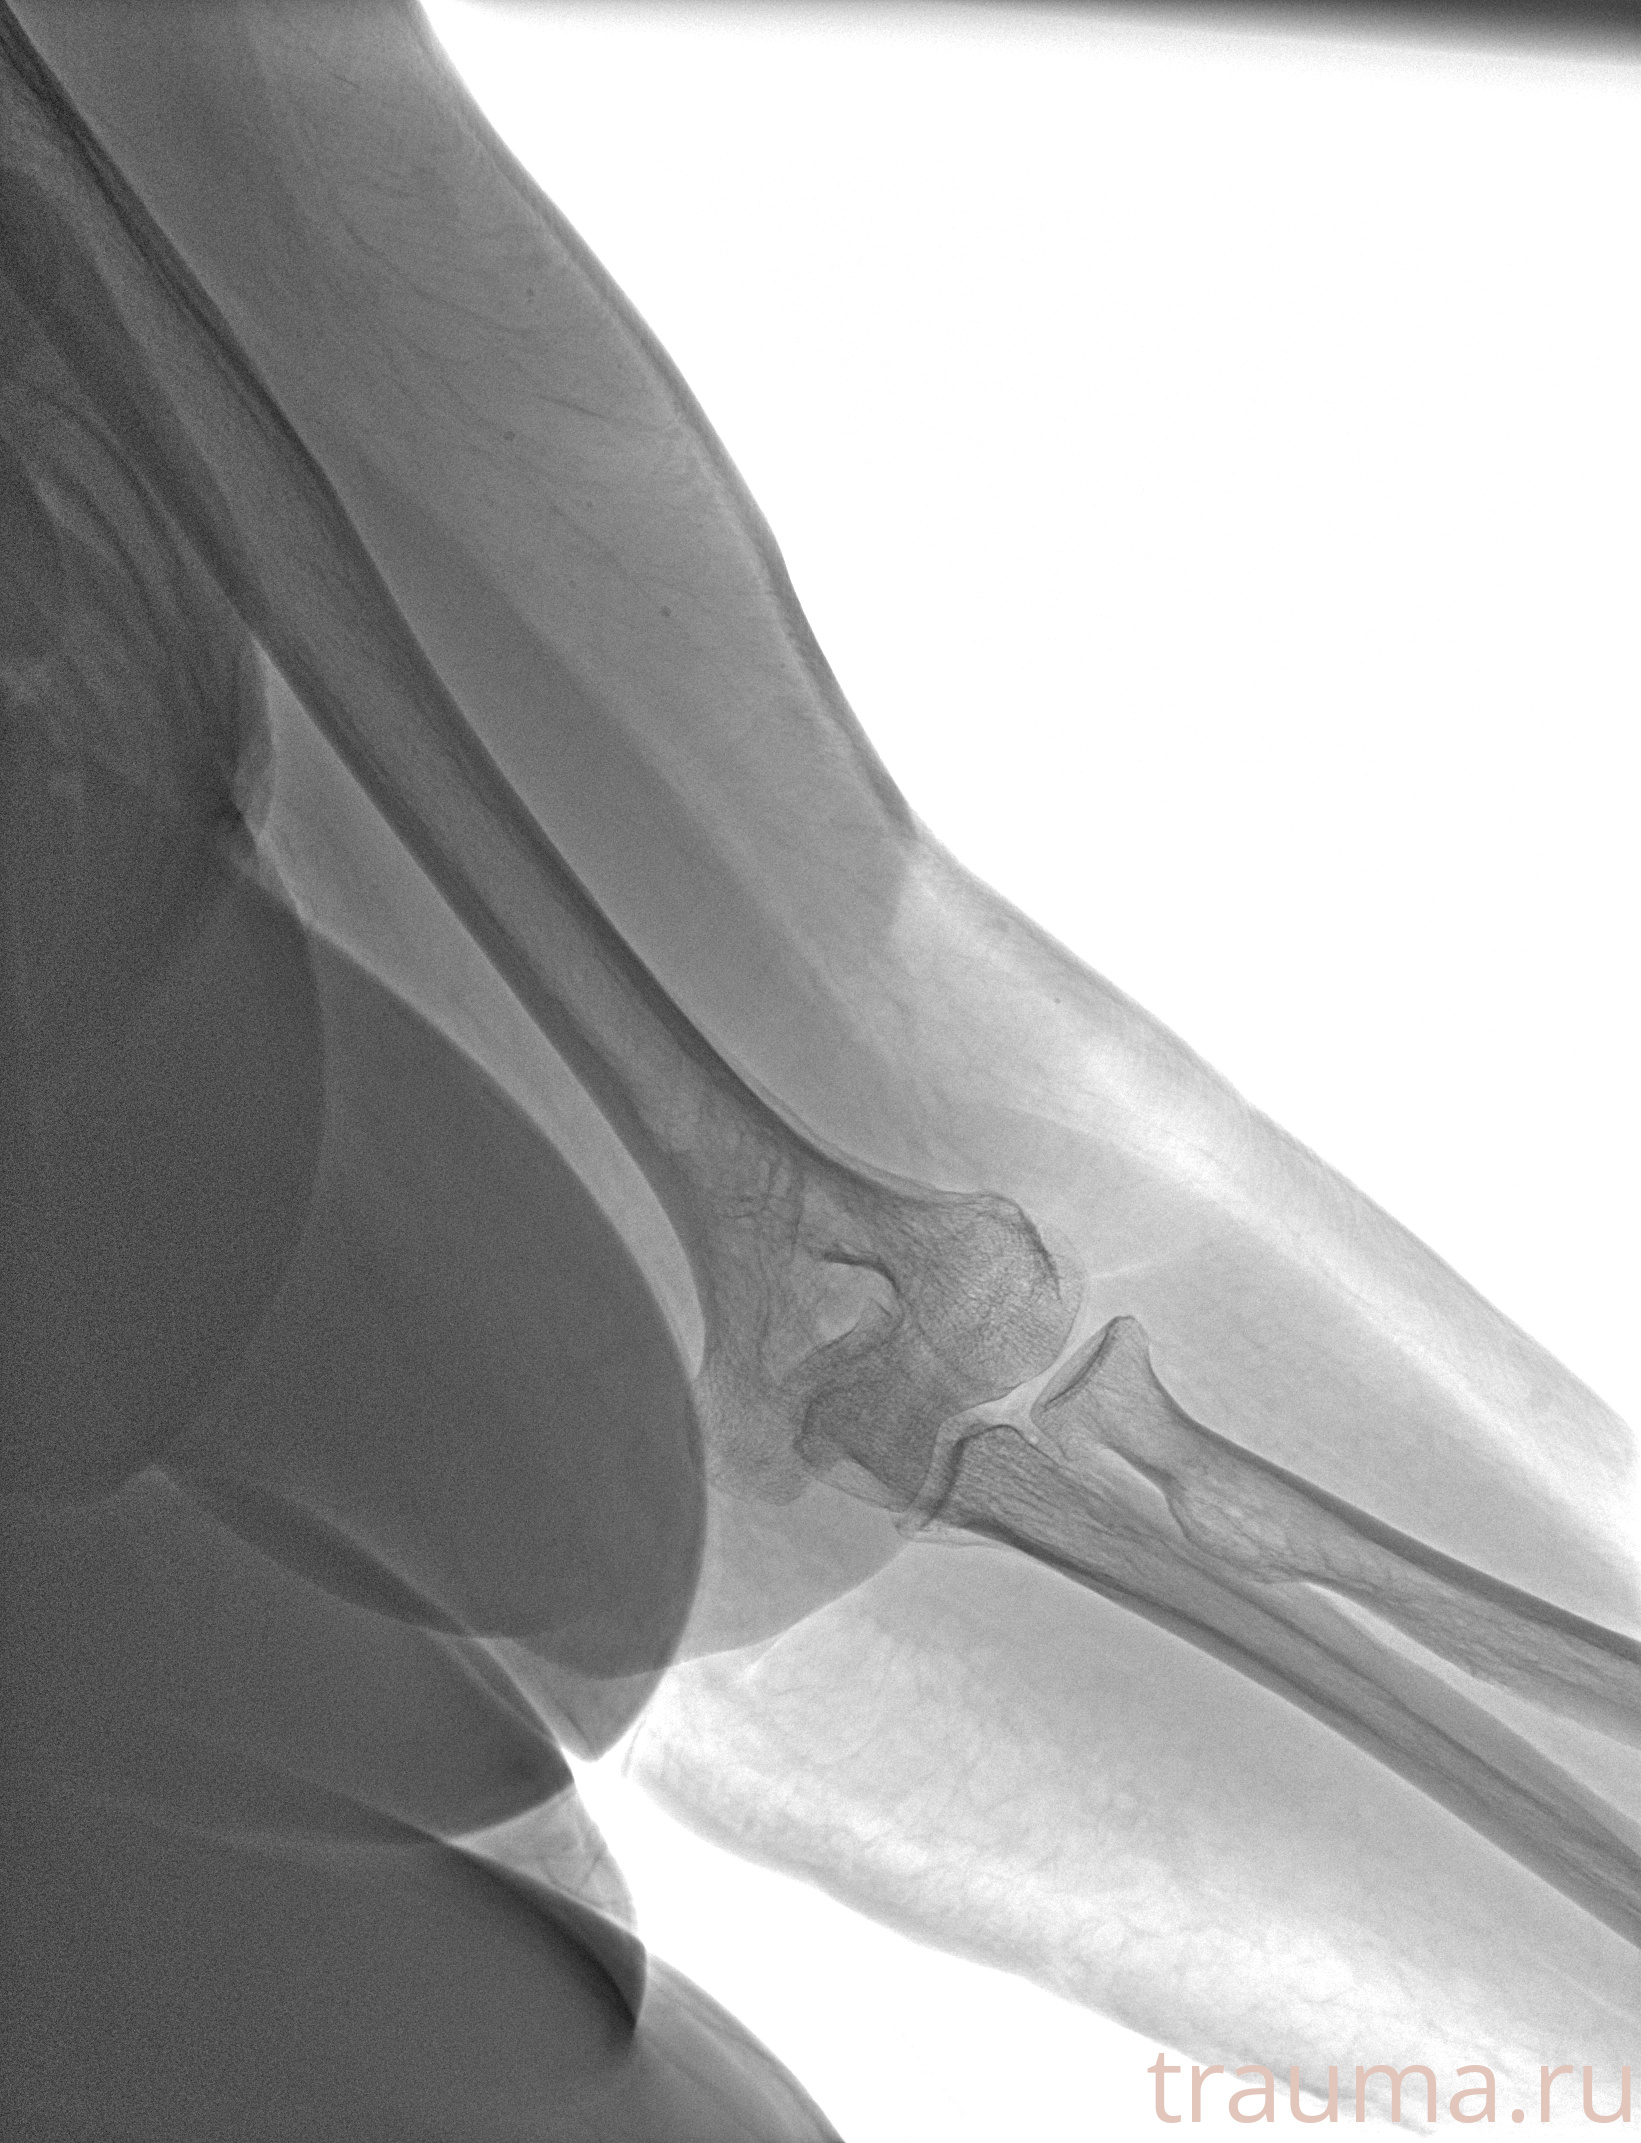

Рентгенограммы

Рентген на дому: по вашему адресу приезжает врач-рентгенолог, травматолог-ортопед с мобильным рентгеновским аппаратом, проводит диагностику травмы или заболевания, делает необходимые рентгенограммы, дает рекомендации по дальнейшему лечению. Получить качественные снимки в домашних условиях возможно благодаря уникальной методике, разработанной МосРентген Центром для института  Склифосовского